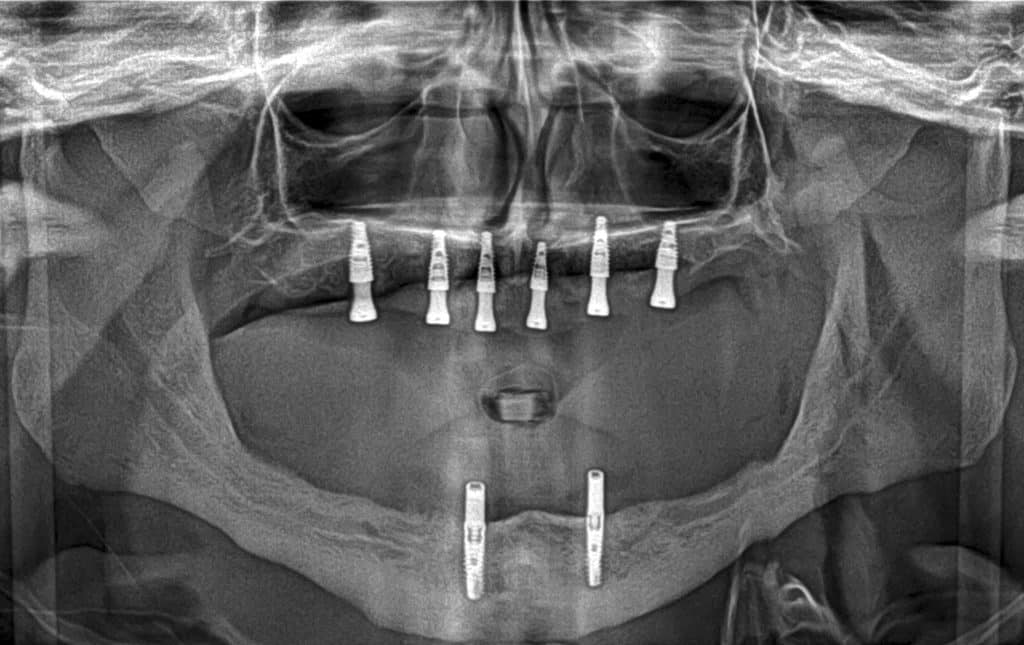

here a case where a full mouth réhabilitation was done by placing 6 implants

multiunit abutement were placed and a temporary bridge also was made for emergence profile shaping